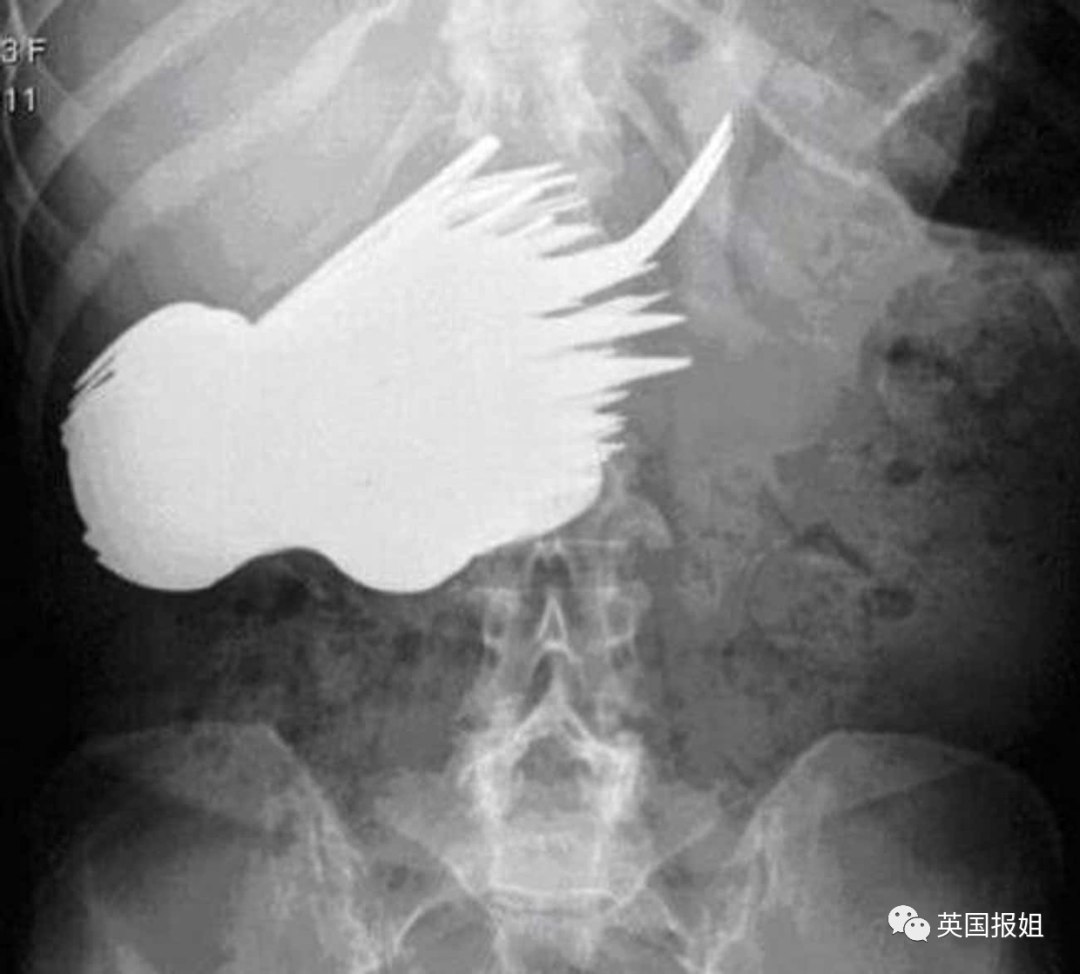

当固体已经满足不了他们的时候,还有人毅然决然选择了流体:这名美国27岁男子用胶枪将融化的黏合剂给自己灌肠,黏合剂进入体内后迅速凝固,坚若磐石: